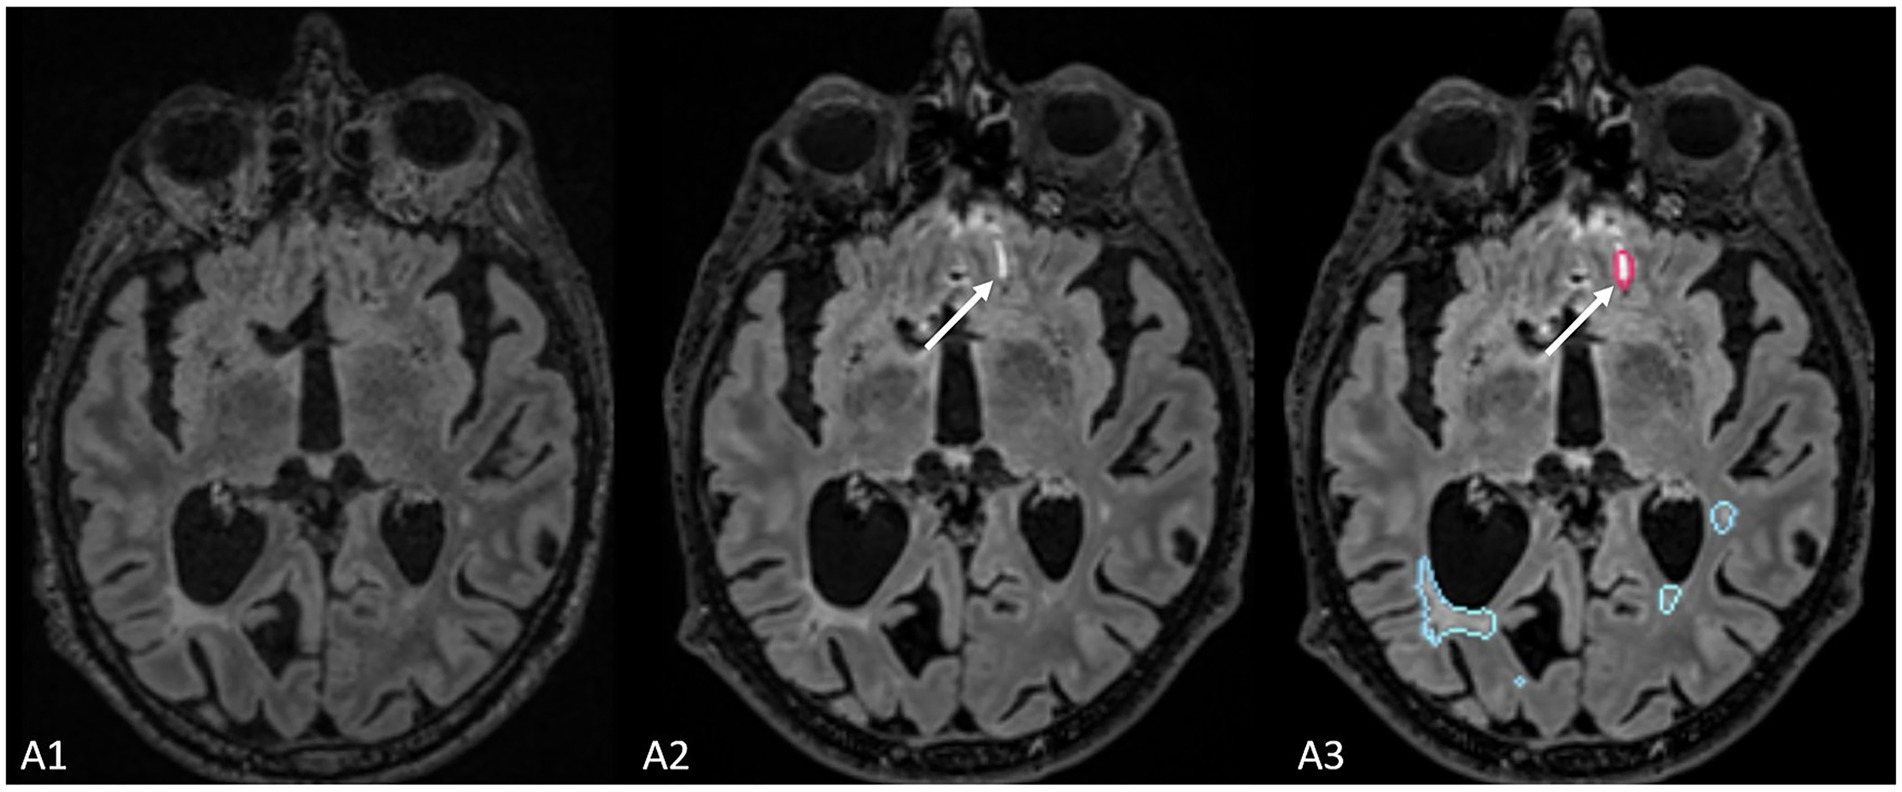

Finally, compared to the ground truth, 61 false positive new lesions were detected by Pixyl.Neuro.MS® software alone, and radiologists did not retain these lesions (Figure 4). False positive lesions were associated with artifacts in 40% (24/61) of cases, while the remaining 60% (38/61) resulted from co-registration errors (28%) and the presence of slowly enlarging lesions (SELs; 26%).

Figure 4. The figure represents a false positive lesion (indicated by the white arrow) which was segmented as a new lesion but actually represents an artifact located at the interface between cerebrospinal fluid and brain parenchyma.

One major consideration for integrating AI into neuroradiology is its effect on workflow efficiency. In our study, the average reading time with AI assistance was 2 min 46 s for Pixyl.Neuro.MS® and 3 min 33 s for Jazz®, compared to an estimated 4 min for neuroradiologists and 8 min for radiology residents in conventional reading reported in the literature (27). A study by Sima et al. (32) showed that the use of AI software resulted in statistically shorter reading times compared to standard radiological reading. Similar results were shown by Peters et al. (28) and Combes et al. (24), who demonstrated shorter reading times when using AI compared to reading times without AI. Even though we did not compare reading times without and with the use of AI, our results suggest a potential time-saving benefit, though this advantage may be offset by the need to verify AI outputs. While AI identifies more lesions, it can also produce false positive results, which need to be validated by radiologists (29). The majority of false positive results in our study were associated with co-registration errors, either only co-registration or linked to the presence of severe atrophy. Additionally, some SELs that were considered new in new exams were reclassified as SELs upon further radiological evaluation. We also encountered artifacts that were mistakenly identified as new lesions. These artifacts typically appear at the boundary where fluid meets the air and the bone, which cannot be completely suppressed in 3D FLAIR sequences (30). This aspect of AI validation may explain why the reading times might even increase in clinical practice.